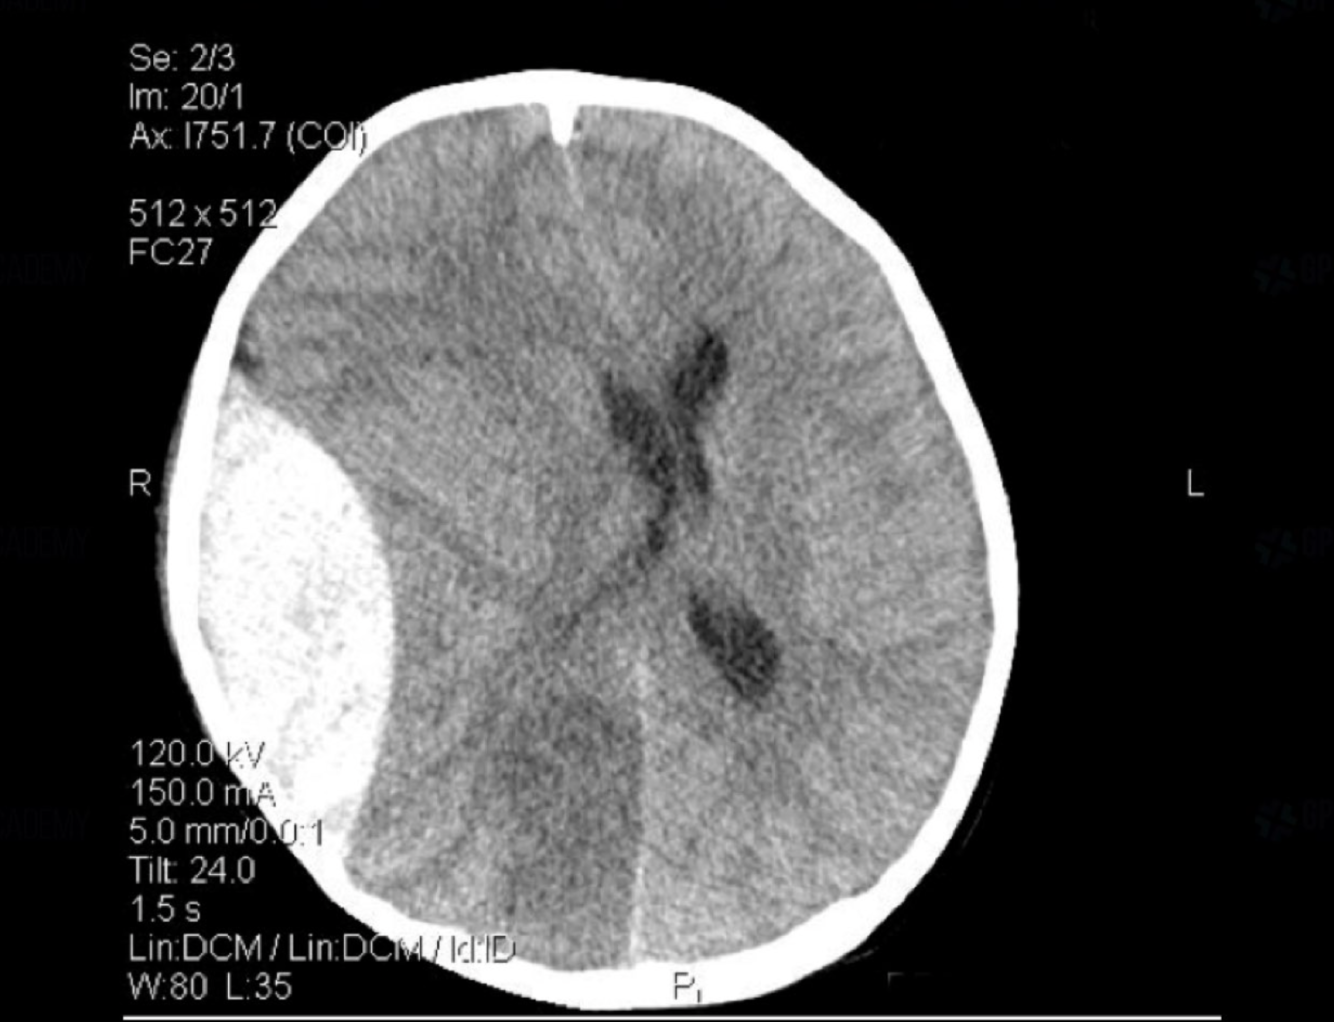

epidural haematoma